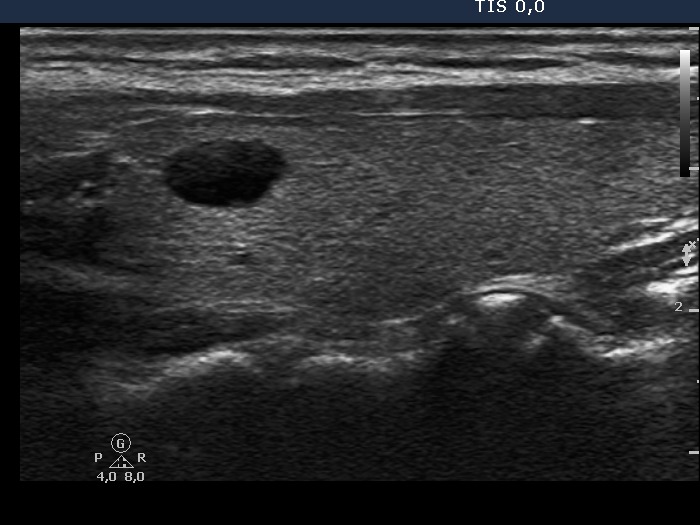

The operated thyroid - case 414 (ultrasonographic picture 6)

Left lobe, longitudinal scan.